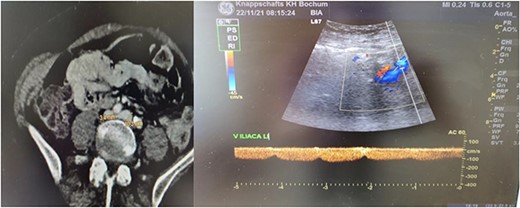

We present the case of a 61-year-old woman who was diagnosed with swelling of the left lower limb for 2 weeks (Fig. 1). She had already been admitted to another hospital and dismissed from the department for vascular surgery after a DVT had been ruled out. Patient history included smoking and regular consumption of alcohol. Trauma, tumor disease, major surgery within 6 weeks before symptom start and prior DVT were ruled out. Patient vitals check showed no abnormalities. When the patient was presented to our department, a DVT was again ruled out by sonography. A CT-angiography and further sonogram of the iliac vessels showed a relevant stenosis of the left common/extern iliac vein (Fig. 2).

Radiological findings. Thrombosis of the left common/extern iliac vein as seen upon CT-scan and sonography.